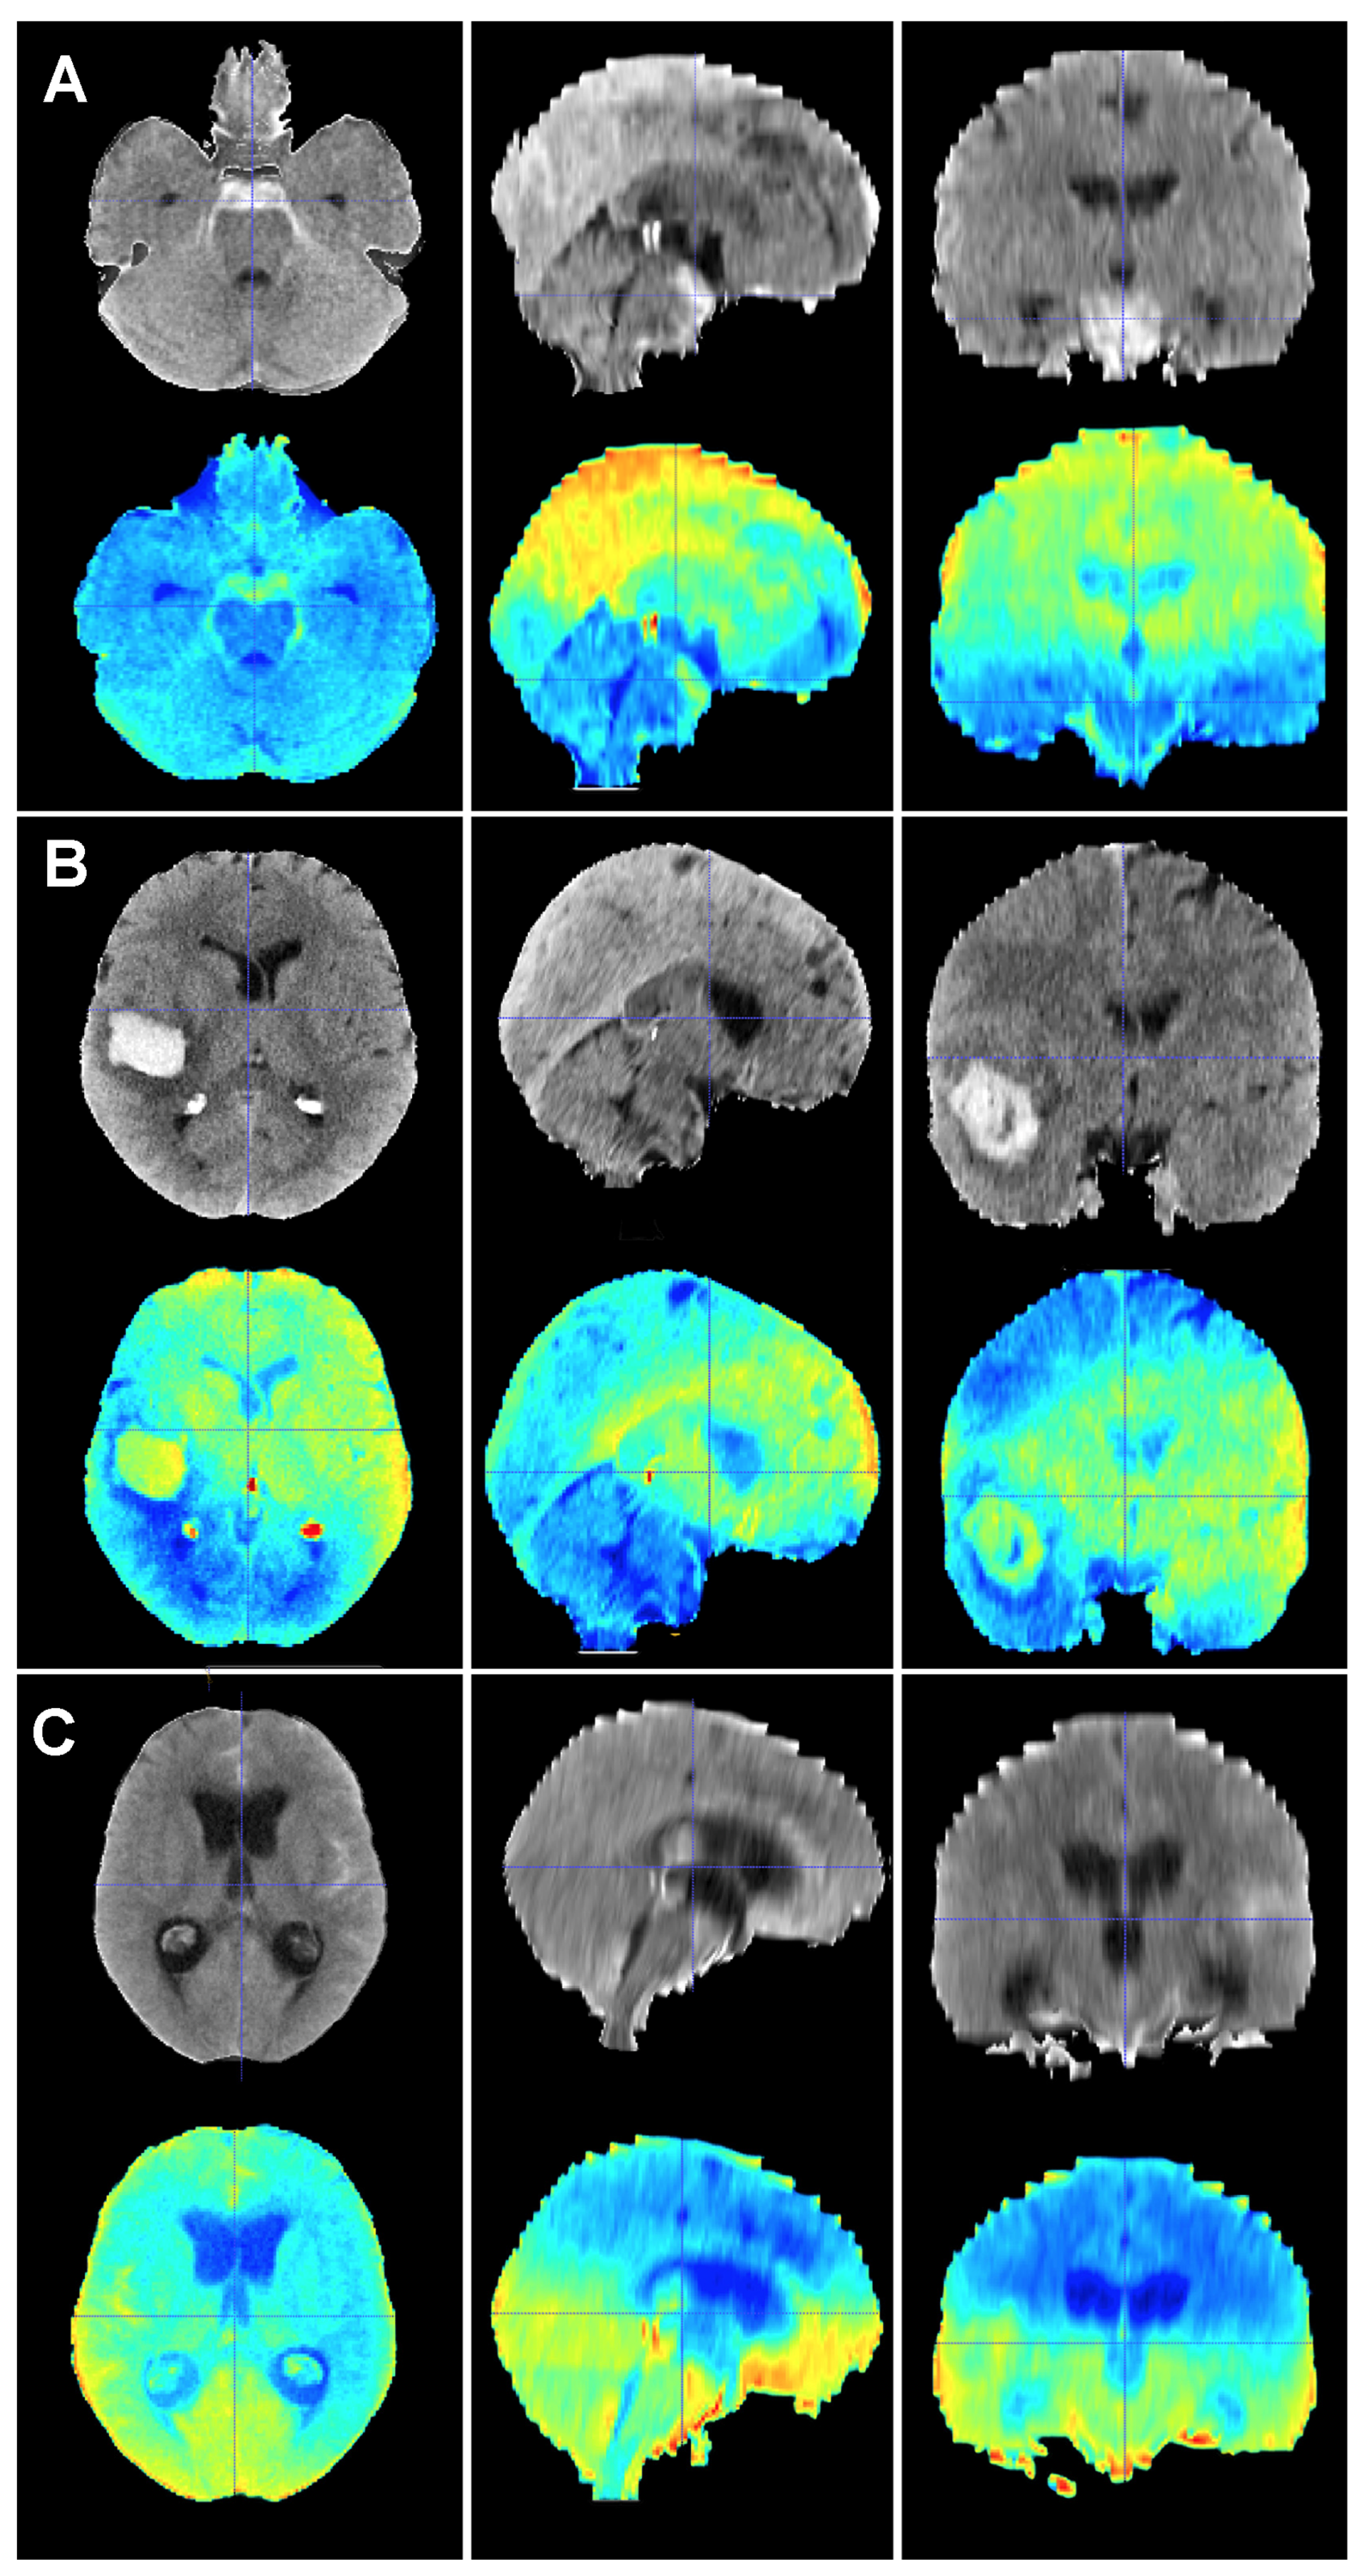

Figure 5.

Baseline CT scan (upper row) and gradient-weighted class activation mapping or Grad-CAM (lower row) for three patients (A–C) from the test cohort who were alive three months after suffering a subarachnoid hemorrhage. Saliency maps highlighted regions in red that were more significant when classifying patients; in this case, into the group of patients who survived the event. Thus, it was possible to create a visual depiction of the process the model followed to allocate patients into each class. These maps highlighted supratentorial brain areas and seemed to disregard hemorrhages, except when they followed a perimesencephalic pattern. (A) A 60-year-old male who suffered a perimesencephalic SAH whose angio-MR and angiography were negative. (B) A 43-year-old male who was diagnosed with a SAH caused by a right middle cerebral artery aneurysm. He was admitted in good condition (WFNS 1) and was surgically treated and discharged without major neurological deficits on postoperative day 19. (C) A 75-year-old female who suffered a SAH and was admitted to the hospital with a WFNS grade 4. The left posteroinferior cerebellar artery aneurysm was coiled. The patient survived the event, but was still severely impaired at the three-month follow-up (modified Rankin Scale: 4).